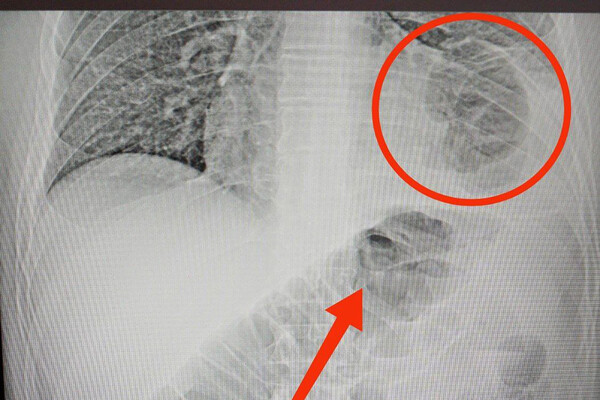

46-летний мужчина обратился в медицинское учреждение с жалобами на боли в животе. В ходе обследования медики обнаружили, что в грудной клетке пациента находится часть кишечника. Оказалось, у мужчины была ущемленная грыжа диафрагмы – редкое состояние, при котором органы брюшной полости через отверстие в диафрагме попадают в грудную клетку.

Причиной патологии могло стать ножевое ранение, полученное нижнекамцем восемь лет назад. Было принято решение о проведении хирургического вмешательства.

«Врачи аккуратно извлекли ущемленную кишку из грудной клетки, проверили, нет ли омертвевших участков. После устранили дефект диафрагмы, зашив отверстие», - сообщили в Минздраве.